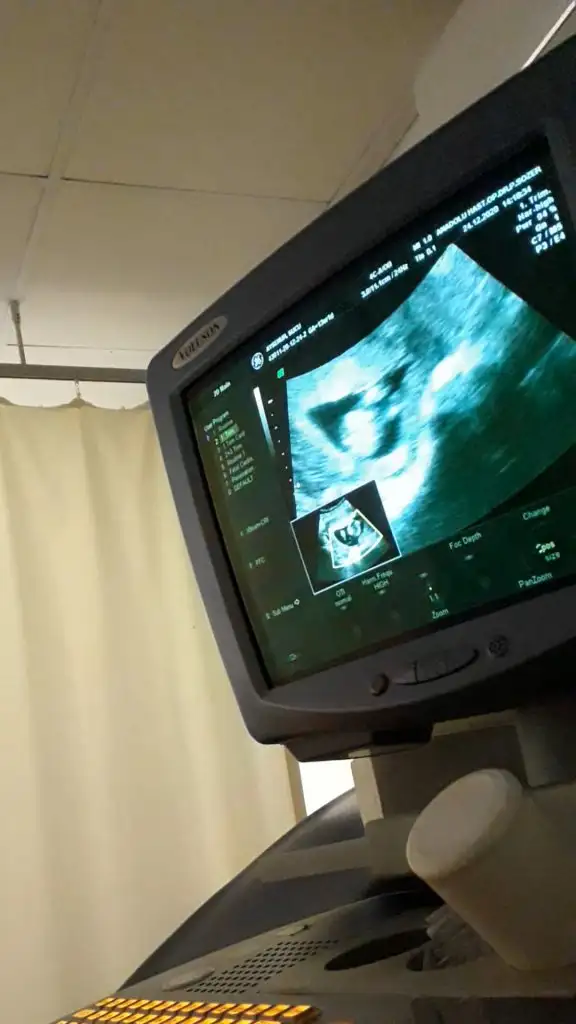

Ikra meyra Ikra meyra canım bana da yorum yapabilirsen çok sevinirim🤗

şu çıkıntı nubsa benim çok net sanki 😂

11+0 bu arada